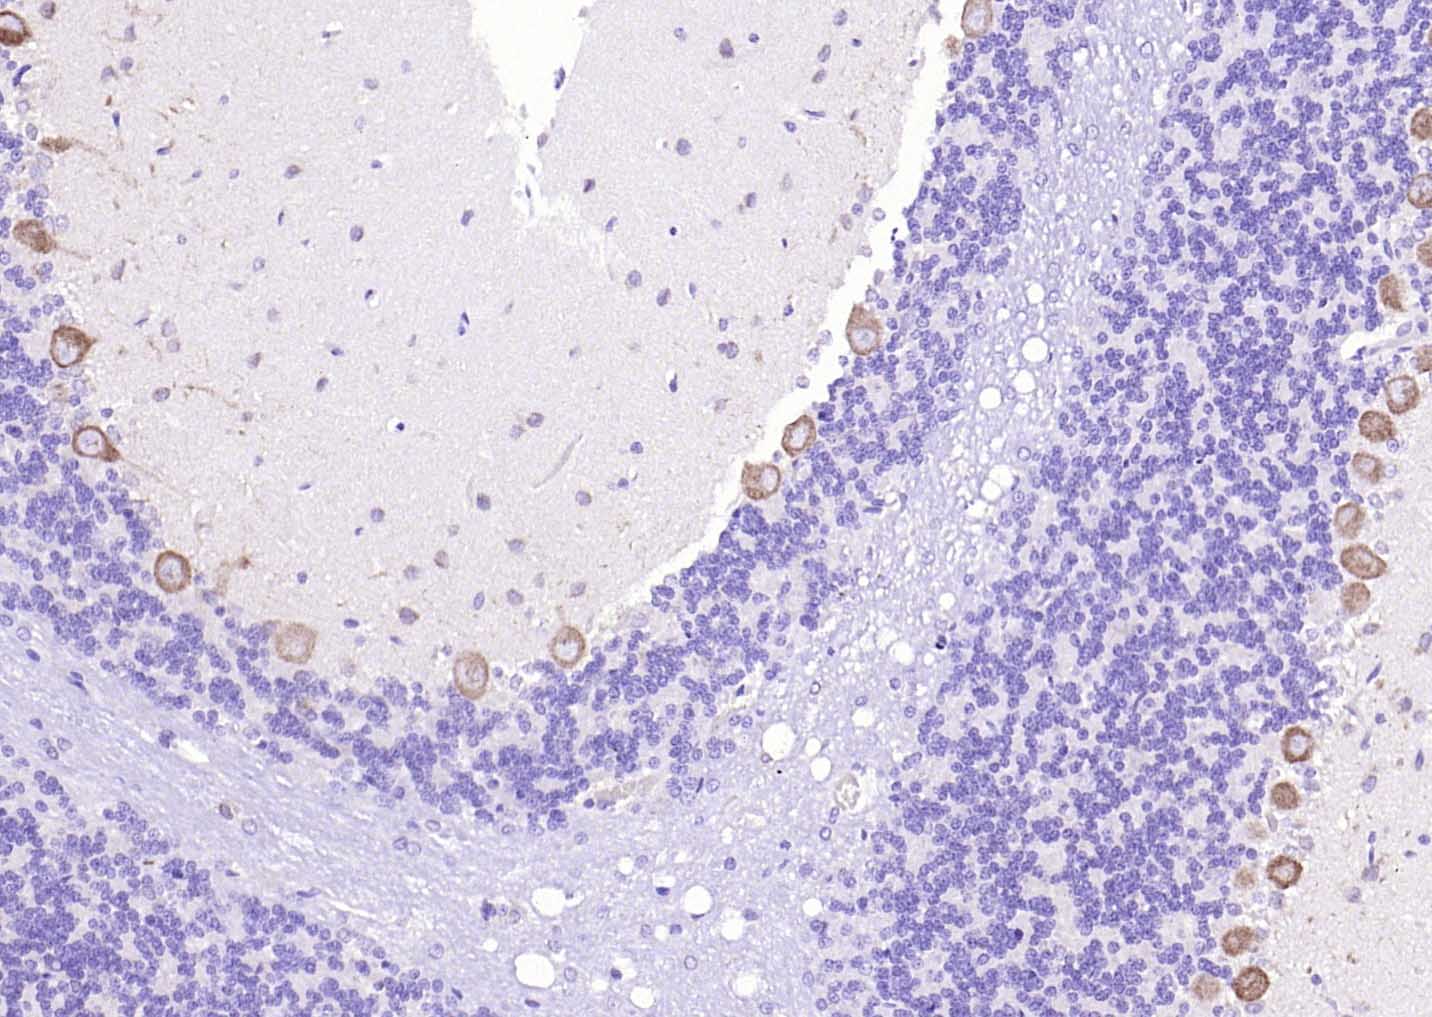

Paraformaldehyde-fixed, paraffin embedded (mouse cerebellum); Antigen retrieval by boiling in sodium citrate buffer (pH6.0) for 15min; Block endogenous peroxidase by 3% hydrogen peroxide for 20 minutes; Blocking buffer (normal goat serum) at 37°C for 30min; Antibody incubation with (CACNA1G + CACNA1H) Polyclonal Antibody, Unconjugated (bs-11984R) at 1:200 overnight at 4°C, followed by operating according to SP Kit(Rabbit) (sp-0023) instructionsand DAB staining.

Paraformaldehyde-fixed, paraffin embedded (rat cerebellum); Antigen retrieval by boiling in sodium citrate buffer (pH6.0) for 15min; Block endogenous peroxidase by 3% hydrogen peroxide for 20 minutes; Blocking buffer (normal goat serum) at 37°C for 30min; Antibody incubation with (CACNA1G + CACNA1H) Polyclonal Antibody, Unconjugated (bs-11984R) at 1:200 overnight at 4°C, followed by operating according to SP Kit(Rabbit) (sp-0023) instructionsand DAB staining.